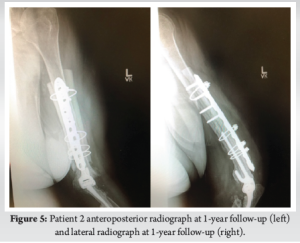

At 5 months, the patient’s incision was healed nicely. They were able to achieve 20° short of full extension and flex up to 120°. Pronation and supination were near the full range of motion. Sensation was intact with 5/5 strength in wrist, finger, and thumb extension. Anteroposterior and lateral X-rays showed proper consolidation of the fracture. At 1-year follow-up, the patient was able to use her arm and did not note any new problems. The left arm showed well-healed incisions with a similar functional range of motion. Anteroposterior and lateral X-rays confirmed proper consolidation of the fracture (Fig 5).